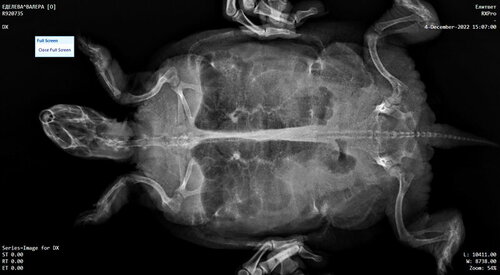

Лечение назначенно,сделан снимок ,расшифровать не кому,ждём результаты с Москвы,сдали клинику и биохимию.

Мне нужно как-то расшифровать результаты анализов и снимок,тк таких специалистов в городе нет, соответственно лечим по первоначальной схеме.